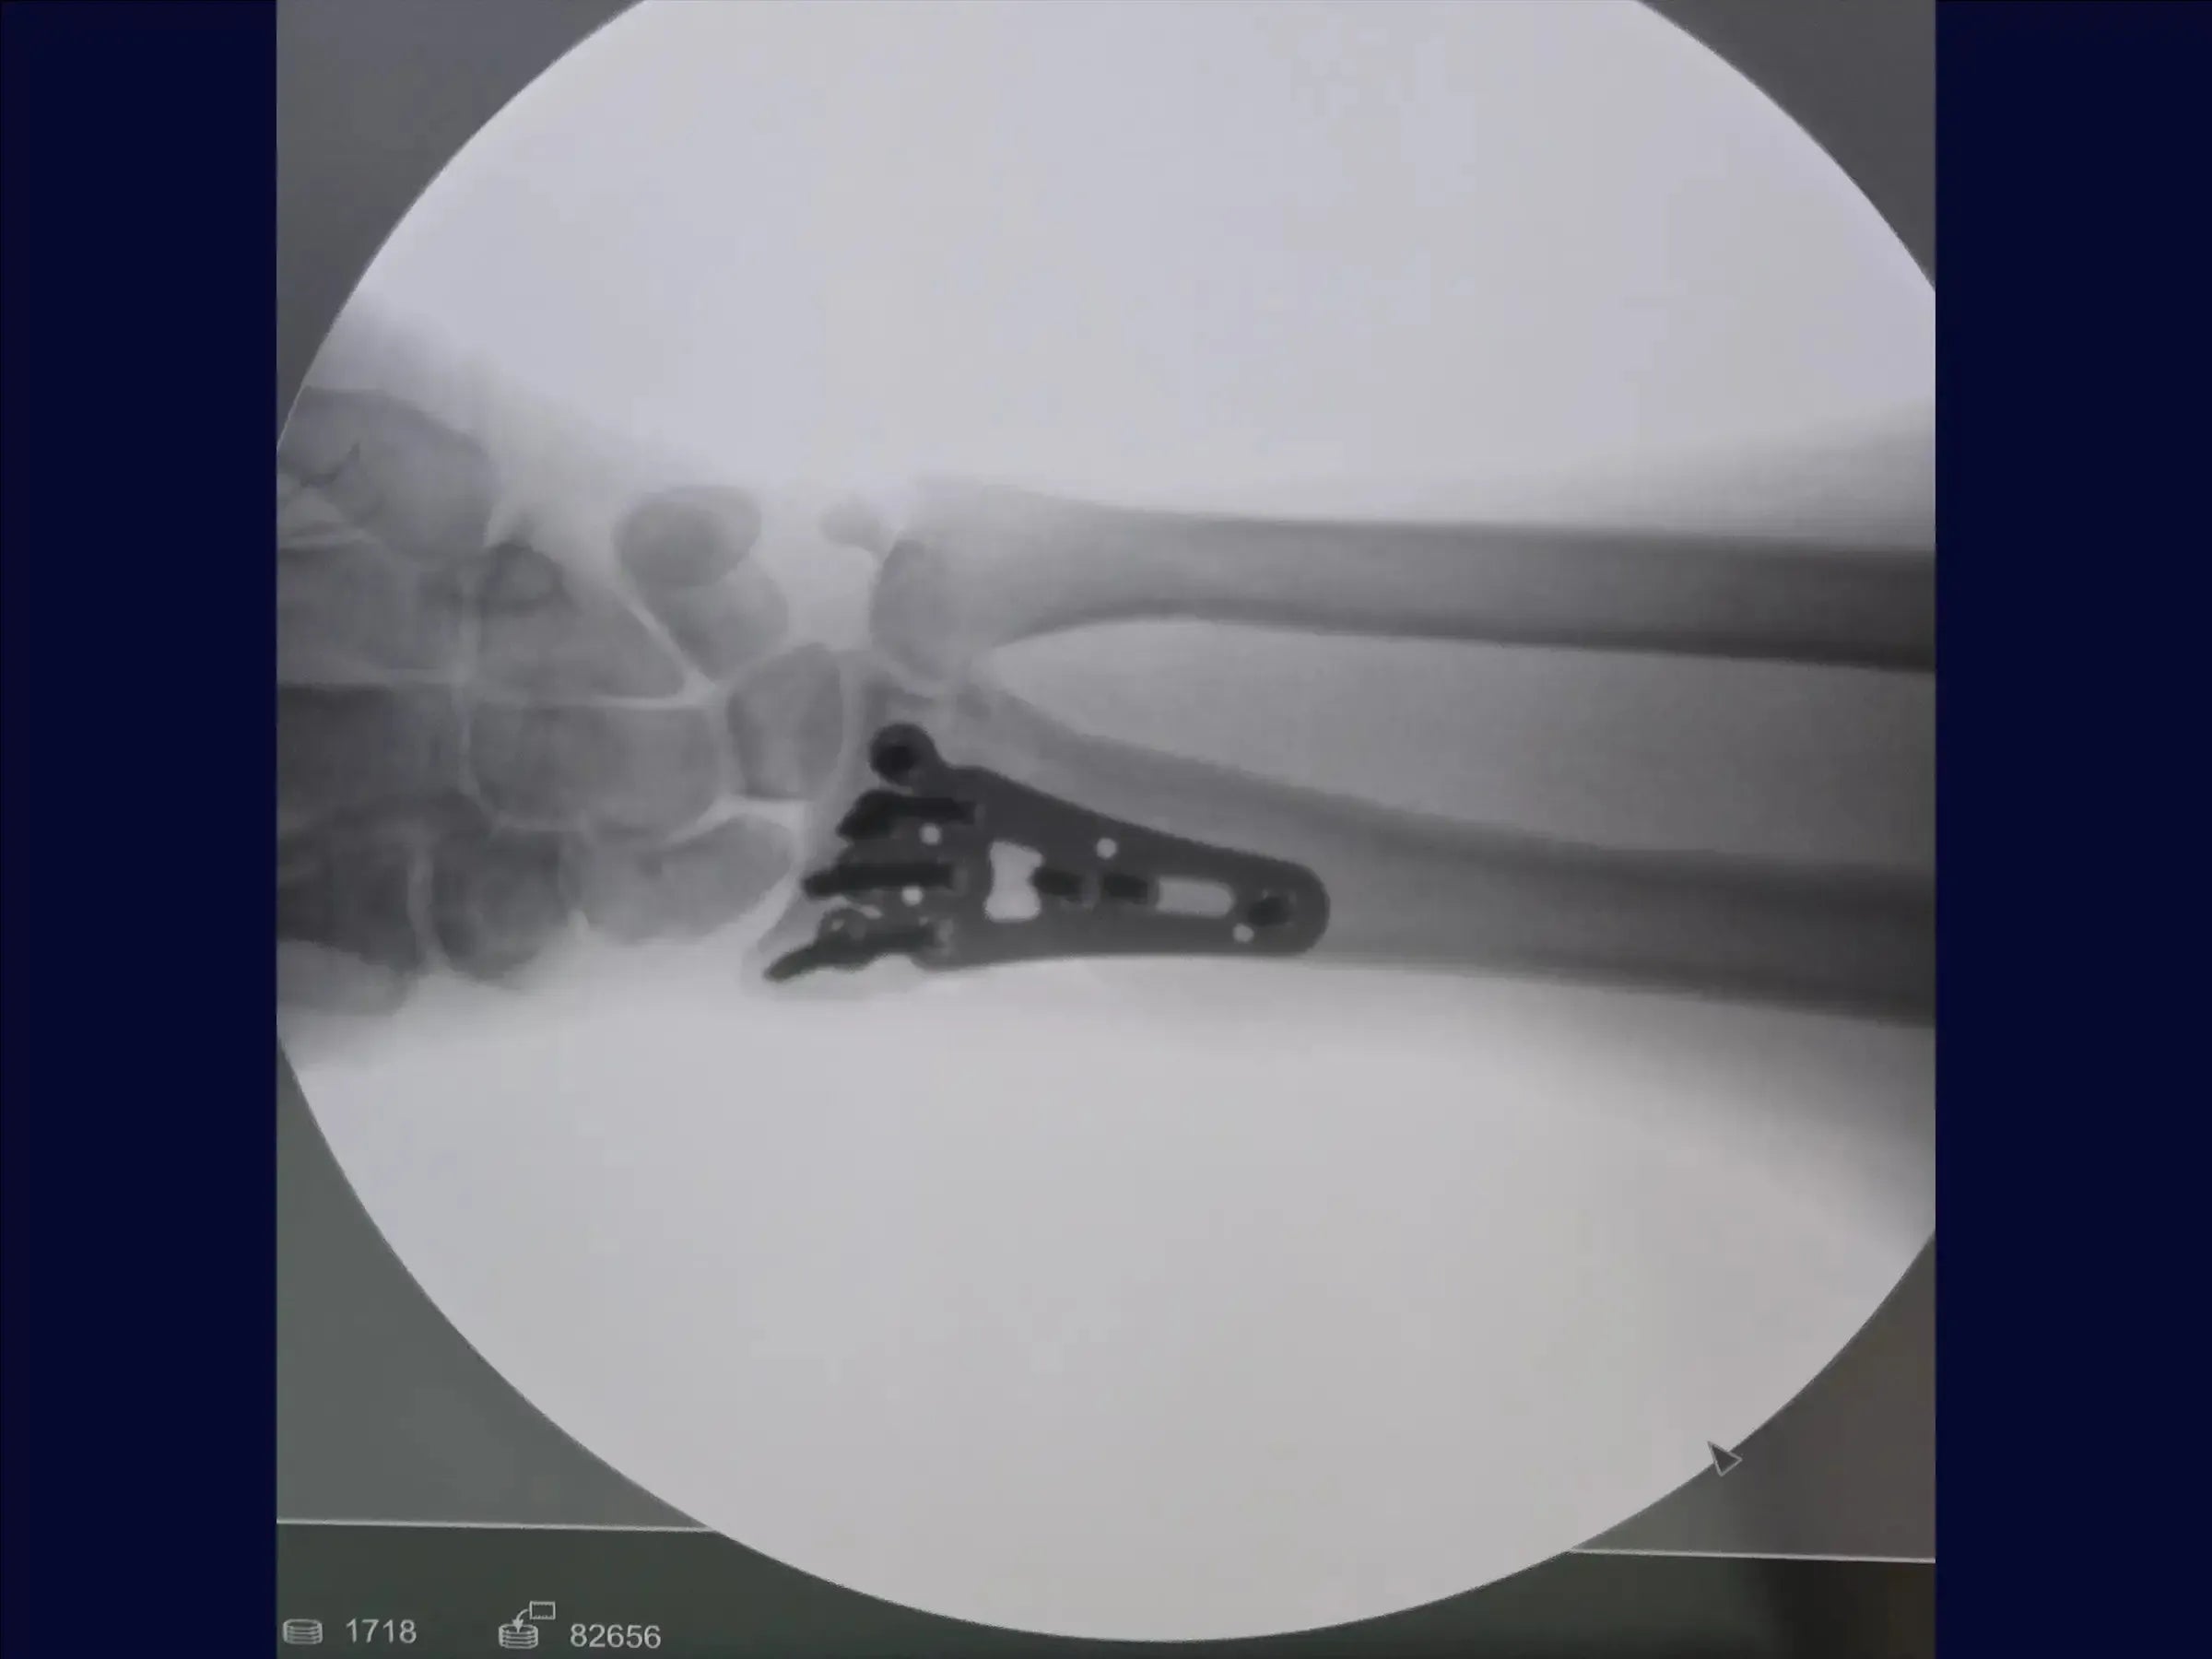

- Exposição do Rádio e Implantação da Placa: O rádio é exposto, e um descolador é utilizado para preparar o leito da placa. Com a fratura já reduzida pela fixação provisória, a colocação dos parafusos deve respeitar a inclinação radial para evitar que fiquem intra-articulares. É recomendado manter a redução manualmente ou usar fios adicionais para evitar perda de redução.

- Fechamento e Resultados: O acesso através do pronador quadrado é suturado para cobrir a placa. O resultado final é satisfatório, com parafusos bem posicionados, inclinação radial mantida e fratura bem fixada. O fechamento é realizado por planos até a pele.